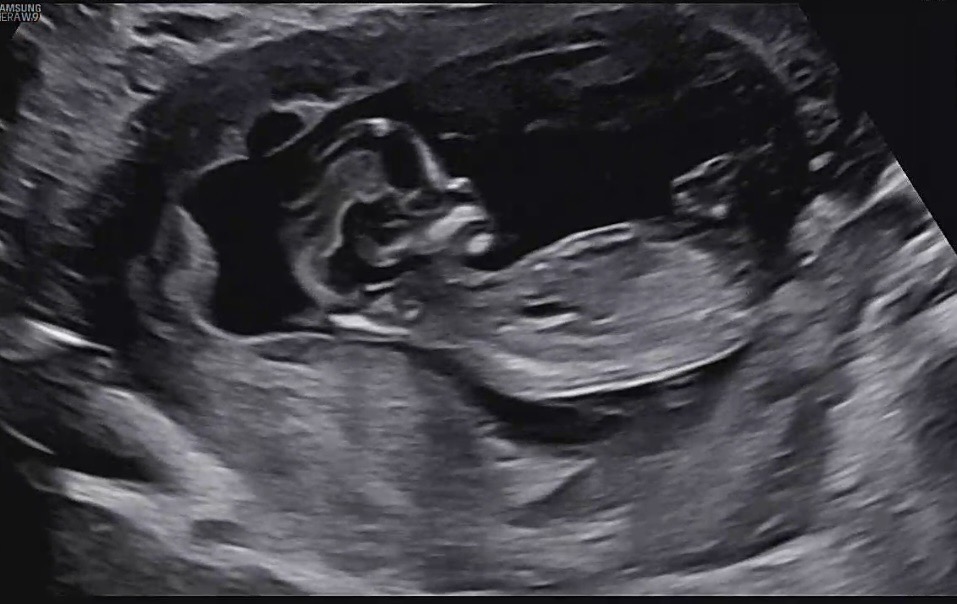

12주에용 성별 각도법 한번 봐주셔용🥹

아들일까용 딸일까용 🤭